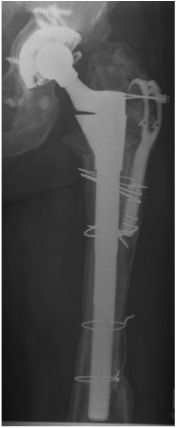

2. Extensively porous coated diaphyseal fitting uncemented stem

- Paprosky Types I, II, IIIA

- 90- 95% 10 year survival

- fracture

- stress shielding with additional proximal bone loss